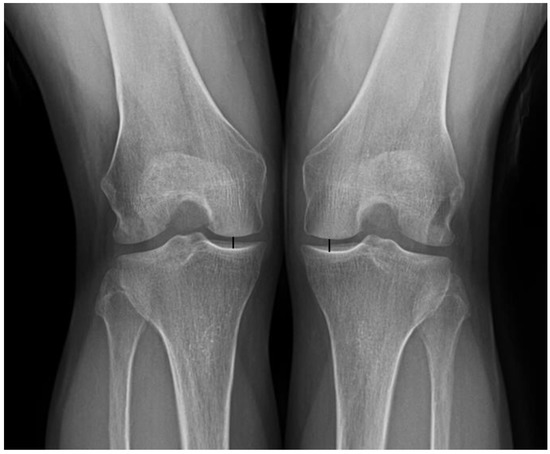

| IKDC radiographic scale ‡ | 0.139 | ||

| A | 24(70.6%) | 76(82.6%) | |

| B | 10(29.4%) | 16(17.4%) | |

| Height of joint space, mm | |||

| Affected side † | 4.8 ± 0.5 | 4.9 ± 0.4 | 0.219 |

| Unaffected side † | 4.9 ± 0.4 | 4.9 ± 0.4 | 0.154 |

| IKDC radiographic scale ‡ | <0.001 | 0.152 | 0.003 | ||||

| A | 24(70.6%) | 15 (44.1%) | 76(82.6%) | 66 (71.7%) | |||

| B | 10(29.4%) | 17 (50%) | 16(17.4%) | 25 (27.2%) | |||

| C | 0(0%) | 2 (5.9%) | 0(0%) | 1 (1.1%) | |||

| D | 0(0%) | 0 (0%) | 0(0%) | 0 (0%) | |||

| Height of joint space (mm) † | |||||||

| Affected side | 4.8 ± 0.5 | 3.8 ± 1 | <0.001 | 4.9 ± 0.4 | 4.7 ± 0.4 | 0.184 | <0.001 |

| Unaffected side | 4.9 ± 0.4 | 4.6 ± 0.4 | 0.273 | 4.9 ± 0.4 | 4.8 ± 0.6 | 0.312 | 0.352 |